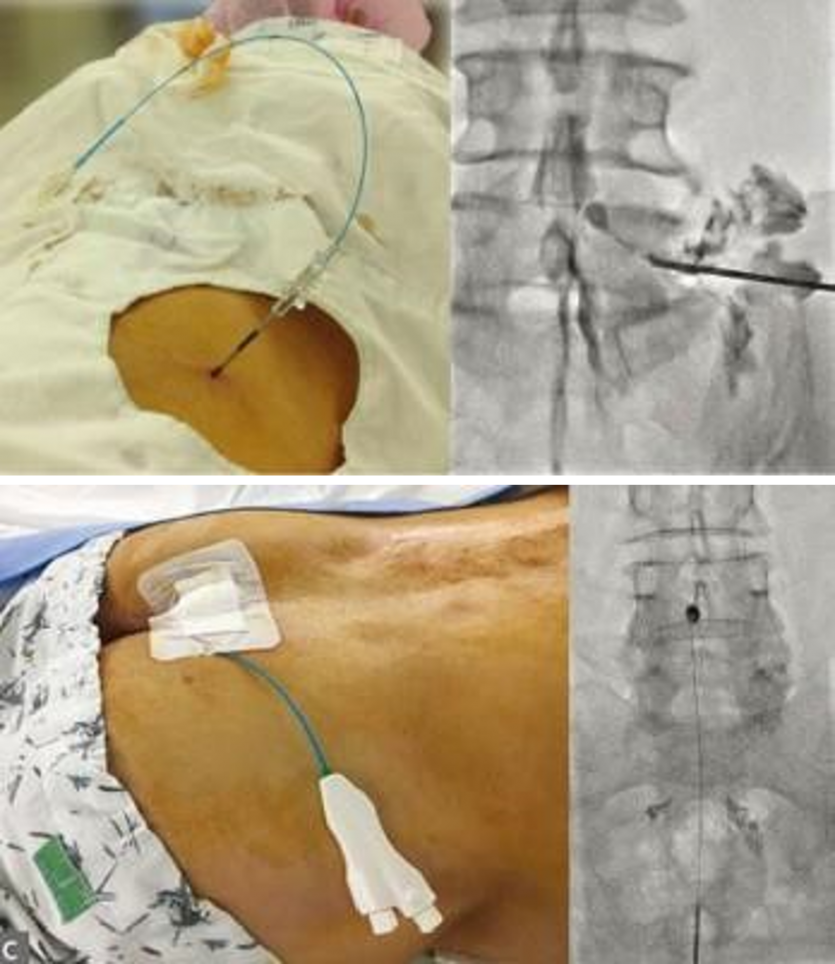

After local anesthesia around the tailbone, a special catheter with a diameter of 1~2mm with a needle is inserted into the affected area to treat inflammation, swelling, and adhesion by injecting high-concentration saline solution and anti-inflammatory enzymes.

Neuroplasty improves the problem of drugs not reaching the lesion and flowing out due to adhered discs and nerve inflammation. It confirms the exact lesion site through real-time imaging and directly injects the drug to eliminate adhesions and relieve inflammation.

This is a treatment method that relieves nerve inflammation by directly administering drugs while checking the treatment area in real time with C-ARM after inserting a thin catheter tube of about 2mm through the tailbone.